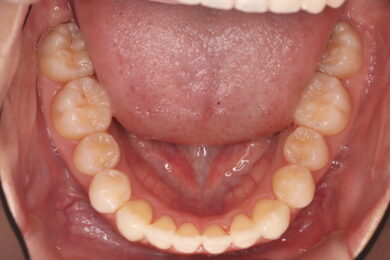

八重歯・叢生 マウスピース矯正(インビザライン)26歳女性 非抜歯

「前歯のガタガタ(叢生)と八重歯を治したい」を主訴に来院された患者様です。上下の歯にIPRを加え、歯列弓の拡大を行い、非抜歯で前歯のガタガタを整えました。顎間ゴムを用い、咬み合わせも改善されています。アライナーの装着時間が長く、チューイをしっかり使用していただけたため、非常に短時間で仕上がりました。

• 治療後